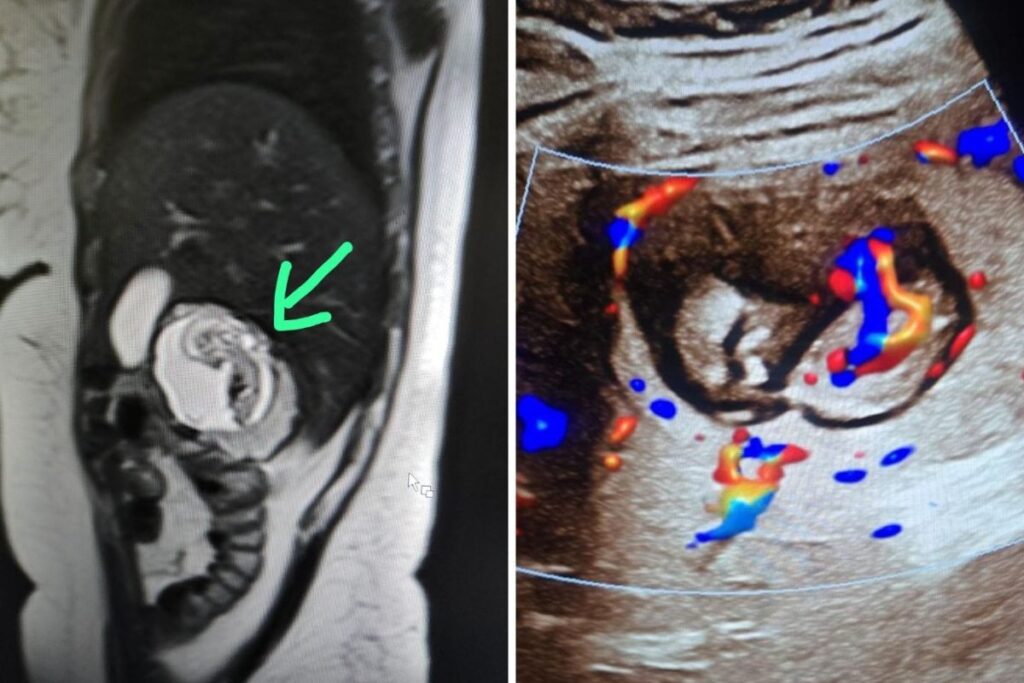

UP Woman’s Foetus Growing In Liver, Not Uterus: What Is Rare Intrahepatic Ectopic Pregnancy?

UP Woman’s Foetus Growing In Liver, Not Uterus: Only 8 such cases reported worldwide. Meerut doctors say this could be India’s first intrahepatic ectopic pregnancy